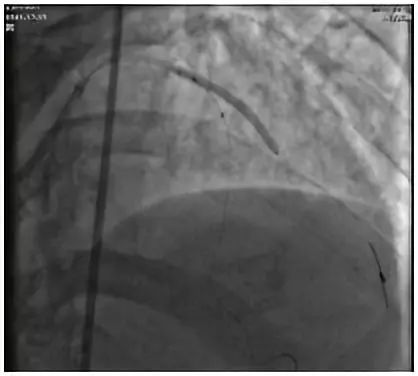

然后使用3.5 X 12mm和3.0 X 12mm球囊进行了第一次分叉病变处的对吻扩张(图11),扩张后于前降支近段植入了3.5X 23mm的火鸟支架(图12),支架植入后再次使用2.0 X 15mm球囊对D1对角支开口处的支架网眼进行了扩张(图13),并使用3.5 X 12mm和3.0 X 12mm球囊进行了第二次分叉病变处的对吻扩张。

微信图片_20190508163425.png图11